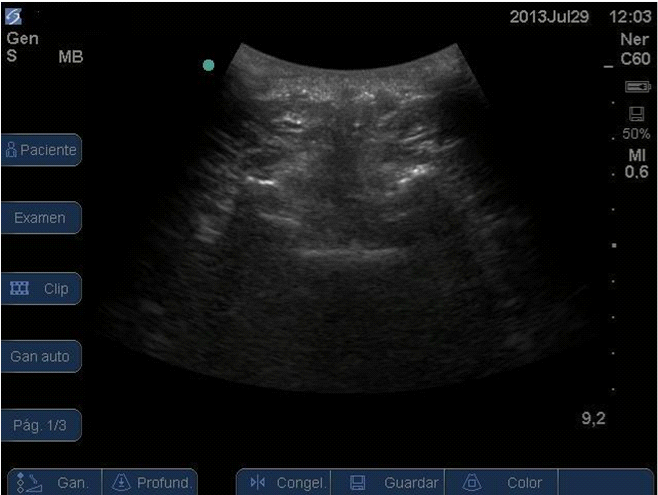

Firstly, a transverse ultrasound scan was done in order to identify and mark midline. Spinous processes could be seen in this view (Figure 1). Secondly, a paramedian sagittal ultrasound scan was performed to identify and mark each intervertebral level, by counting spinous processes or laminae upward from the sacrum. A corresponding skin mark was made at the midpoint of the probe’s long edge (Figures 2 & 3).

Figure 1 Transverse ultrasound scan was done in order to identify and mark midline. Spinous processes (SP) could be seen in this view.